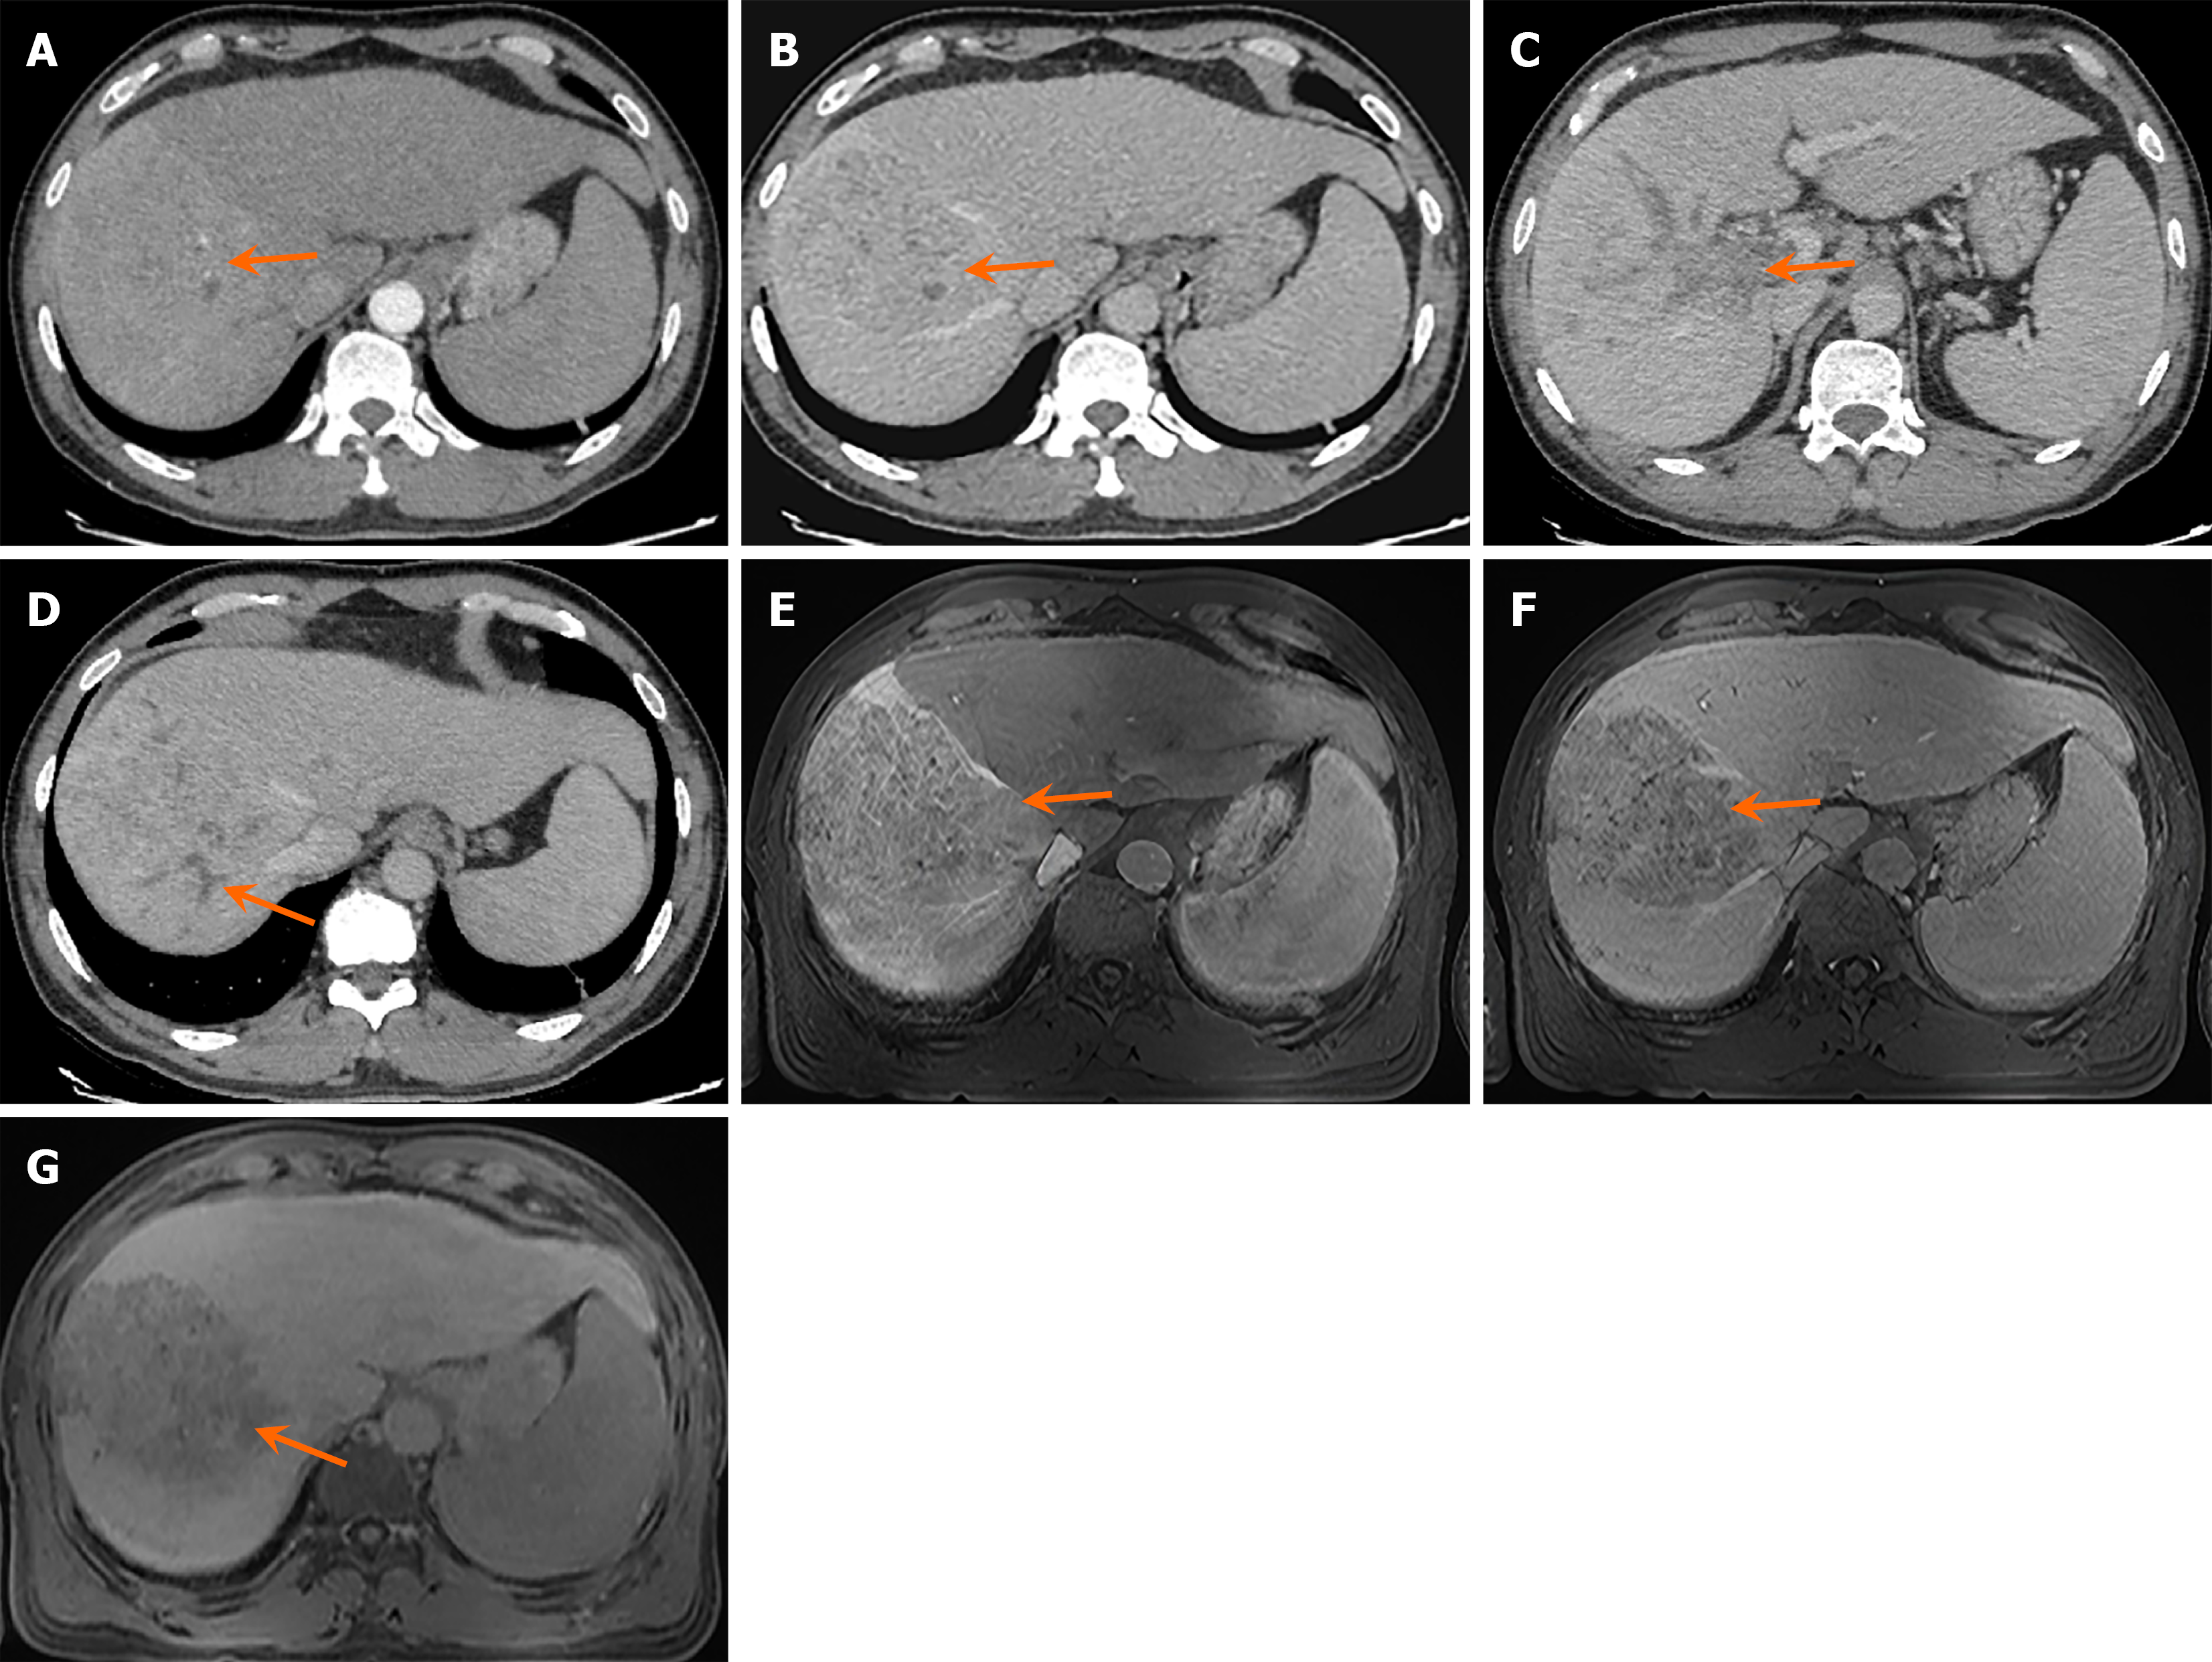

Figure 1 Imaging features of the patient.

A: Arterial phase computed tomography (CT) shows marked enhancement in the right hepatic lobe (orange arrow); B: Portal venous phase CT shows hypointensity in the right hepatic lobe (orange arrow); C: Portal venous phase CT demonstrates visualization of the left branch of the portal vein, but absence of the right branch (orange arrow), suggesting portal vein tumor thrombus; D: Intrahepatic bile duct dilatation is observed (orange arrow), indicating obstructive jaundice; E: Gadoxetic acid-enhanced magnetic resonance imaging (MRI) in the arterial phase demonstrates significant tumor enhancement (orange arrow); F: MRI in the portal/venous phase shows marked hypointensity (washout) of the tumor (orange arrow); G: MRI in the hepatobiliary phase shows marked hypointensity of the tumor due to no contrast uptake (orange arrow).